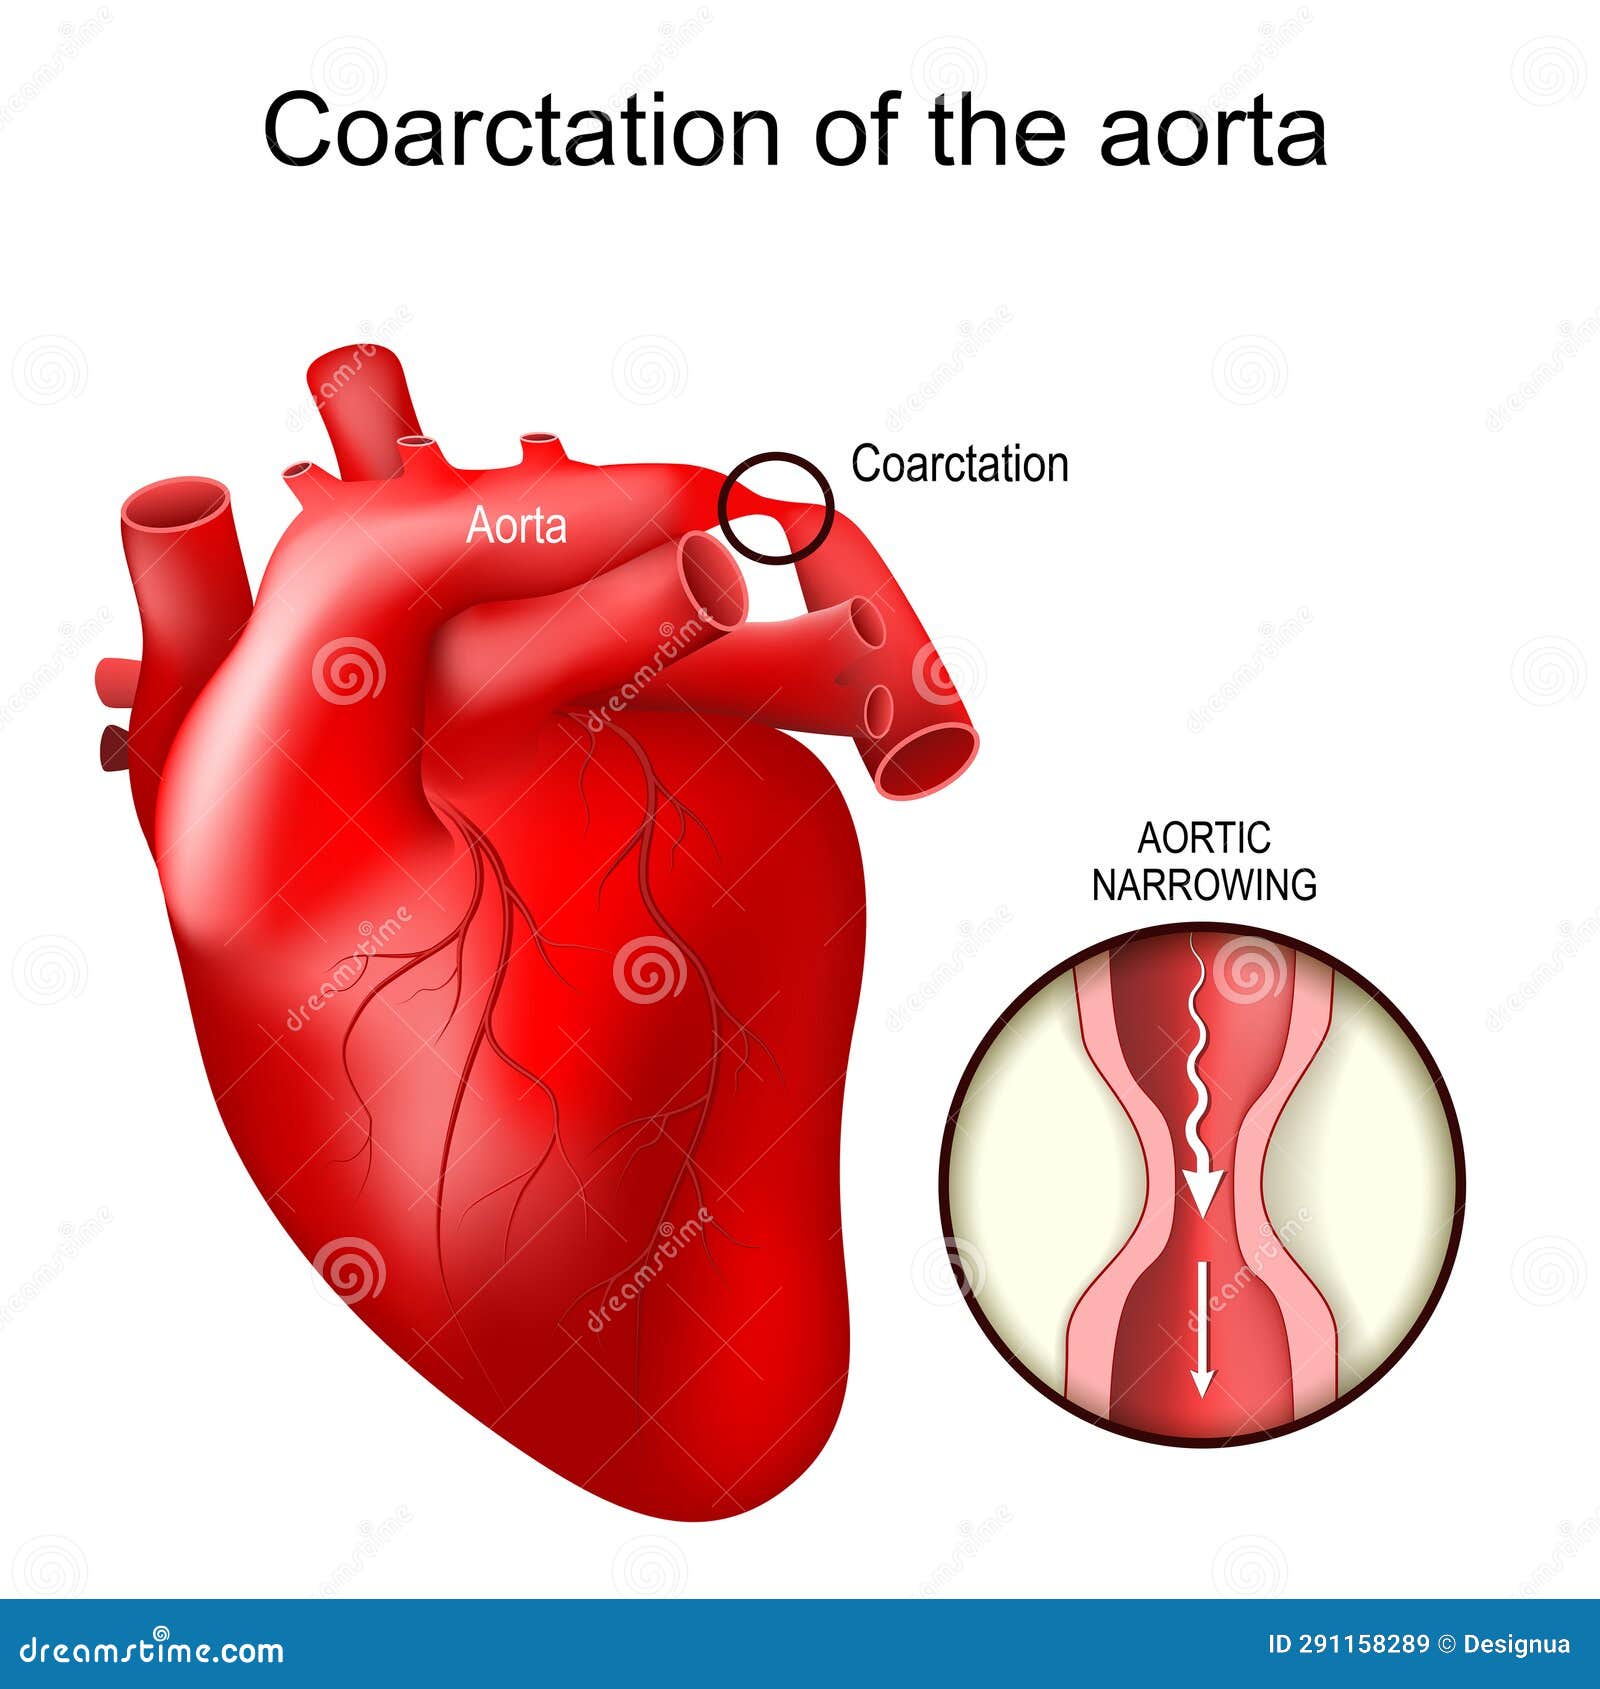

Фотографии и информация о приобретенных пороках сердца